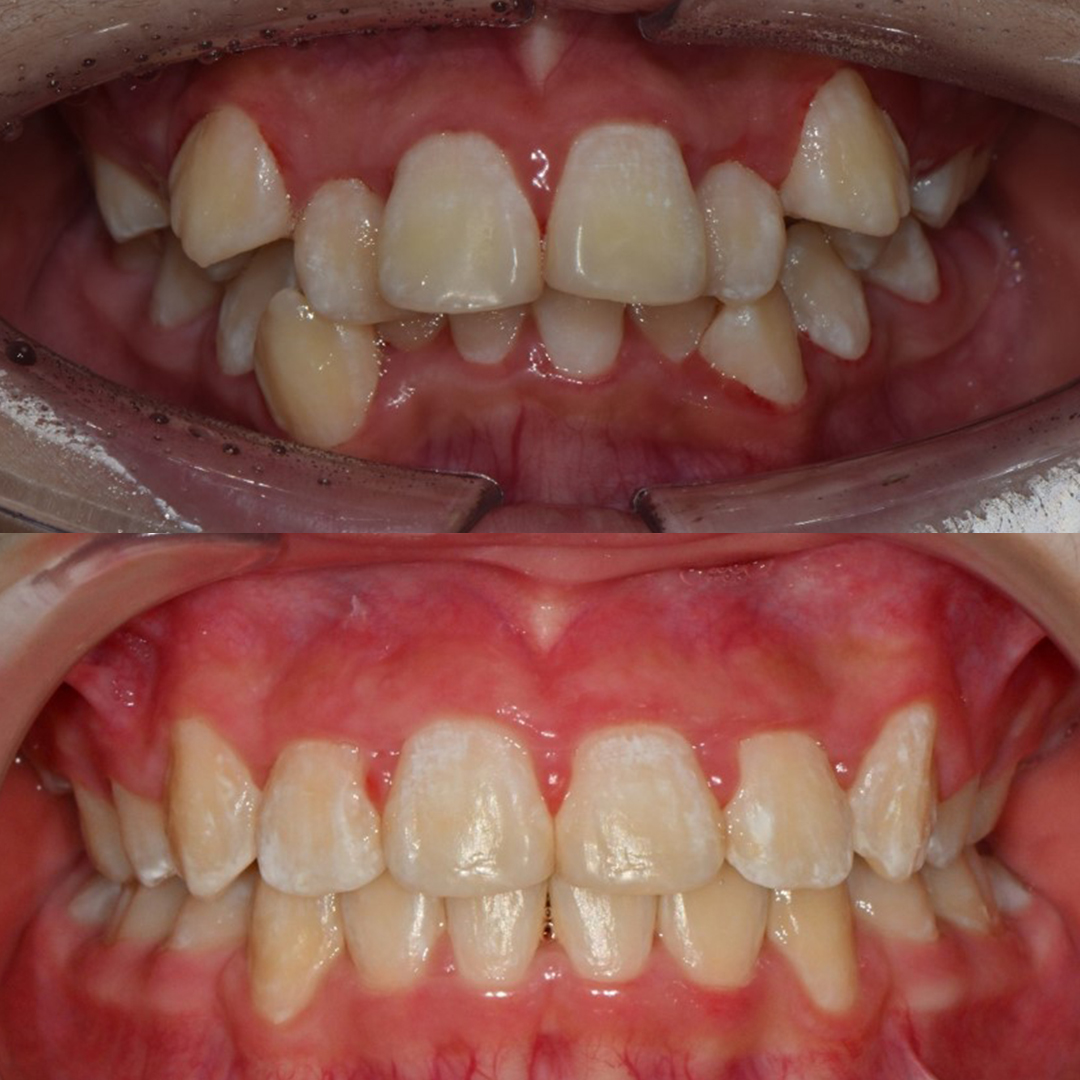

자연치아는 최대한 보존하고 빠른 회복을 위한

최소침습 임플란트

풍부한 임상경험을 토대로 잇몸뼈를 절개하지 않고

빠르고 정확하게 임플란트를 식립하여 붓기와 통증을 최소화합니다.